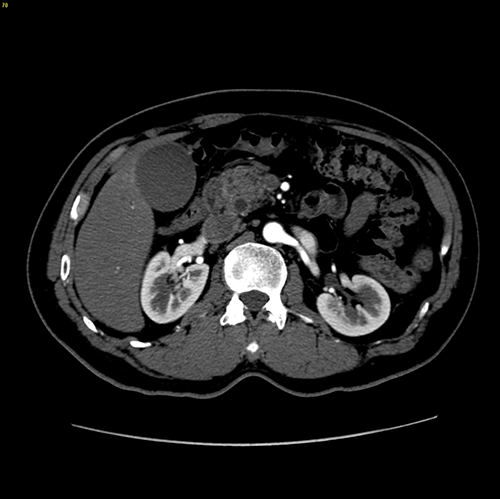

胰头腺癌---胰十二指肠切除